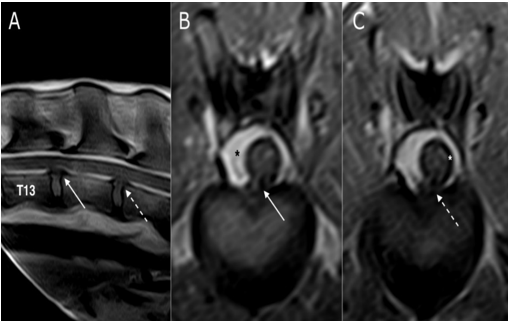

Diagnostic techniques: Blood exams were unremarkable. The dog was anesthetized with medetomidine (sedastart 1 mg/mL, all these are without compression of the spinal cord or sub-arachnoidal space highlighted using a contrast medium. Esteve) at a dose of 3 mcgr/Kg, administered with propofol (proposure 10 mg/mL, Merial) at a dose of 4 mg/Kg and maintained with isoflurane (2.5 %)/vetflurane (1000 mg/g, Virbac). The field of view of the first magnetic resonance imaging (MRI) scanners can was very small (14 cm). As our patient was large, we first performed a CT myelography (Toshiba Asteion dual slice) of the thoracolumbar spine, by intrathecal inoculation at the A after cerebrospinal fluid (CSF) tapping. The slice thickness was set to 3 mm using hard and soft tissue filters. The examination was T1 weighted imaging SET1WI (TE 26, TR 800 ms, Nex 3) on sagittal and transverse planes. The CT myelography can 1) and spin-echo completed using MRI (0.2T unit) (Esaote Vet Mr), with turbo spin-echo T2 weighted imagingTSET2WI (TE 80, TR 2600 ms, Nex revealed spondylosis of the vertebrae from T4 to T7, with multiple disc protrusions on the first lumbartract (Figure 1A-C).

Figure 1: multi-planar reconstruction (MPR) of CT myelography scan on sagittal (A), transverse (B), and dorsal (C) planes. White arrows indicate from T4 up to T7 (A) and at the level of T5-T6 (B) ventral spondylosis. Asterisk shows the disc protrusion in T5-T6 (B) while dashed black arrows (A) indicate multiple disc protrusions in T7-T8 and T8-T9.

This was confirmed as generalized disc degeneration using MRI (Figure 2), at sites T3-T4, T5-T6, T7-T8, T8-T9, T13-L1, and L1-L2, without compressions or signal changes of the spinal cord (Figure 1C, 3B, 4B-C and 5). Widening of the epidural and subarachnoid space was noted (Figure 4 B-C); this alteration was considered secondary to reduced transverse diameter of the spinal cord. CSF was normal on examination. After 23 months, a new MRI was performed using a 0.3T unit (Hitachi Airis II), with turbo spin-echo T2 weighted imaging (TSET2WI= TE 120, TR 5000, and Nex 4), spin-echo T1 weighted imaging (SET1WI= TE30, TR448, Nex 2), and short tau inversion recovery (STIR= TE 25, TI 110, TR 6000, and Nex 2) in the sagittal and transverse planes, confirming the previous findings.